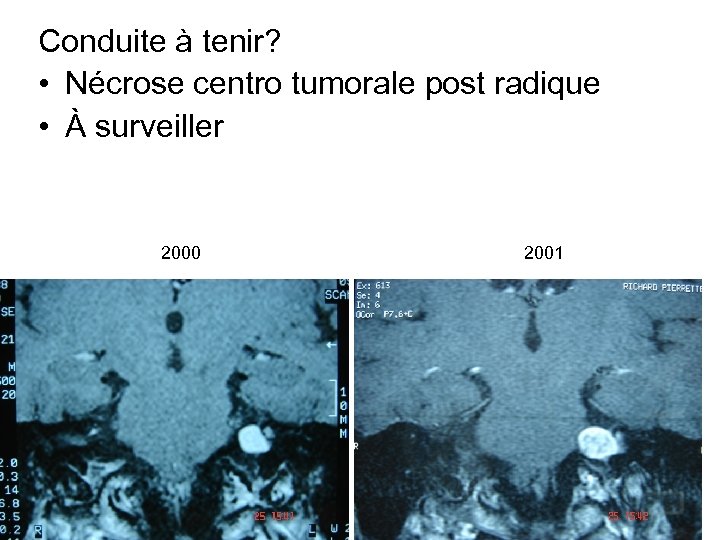

Conduite à tenir? • Nécrose centro tumorale post radique • À surveiller 2000 2001

Conduite à tenir? • Nécrose centro tumorale post radique • À surveiller 2000 2001